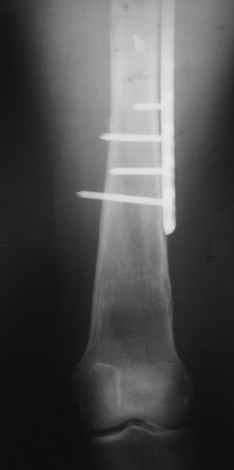

Уважаемые коллеги, приношу извенения за молчание. Готовили материал и боялись писать раньше времени. Все хотели убедиться в том, что после операции все будет спокойно. Спасибо за отклики и советы. К сожалению, гамма-гвоздя, штифтов с возможностью установки более 2-х блокирующих винтов у нас нет. Зато нашли достаточно длинную пластину с угловой стабильностью. После проведения предоперационной подготовки и планирования выполнили остеосинтез. В условиях рентгеноперационной, после репозиции дистрактором из одного разреза 5см в проксимальном отделе подкожно установили пластину. Пришлось выполнить дополнительный разрез до5см в проекции перелома диафиза в средней трети, из которого удалось репонировать перелом и выполнить фиксацию стягивающим винтом. Затем все завершилось наложением пластины с угловой стабильностью. Пластина оказалась достаточно длинной, что позволило перекрыть все переломы с фиксацией каждого отломка минимум 5-ю винтами. Синтез достаточно стабилен. Пациентка активизирована на 3-и сутки(снимки прилагаются). В настоящий момент пациентка выписана на амбулаторное лечение. Еще раз, огромное спасибо всем за помощь в выборе тактики и просто совете. С уважением Украинский Е.

Прошу прощения, со снимками глюк произошел. Высылаю. С уважением Евгений У.

Получилось очень симпатично, мои поздравления. А можно фото конечности без наклеек посмотреть?